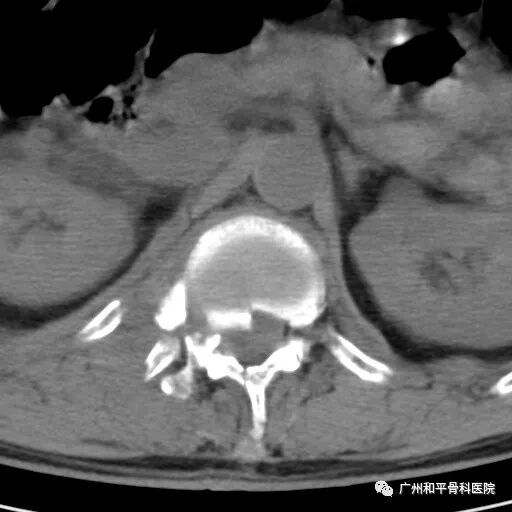

天气炎热,白日晃眼,高空作业要小心。 近日,广州一名工地工人在高空作业的架子上踩空差点摔成“瓷娃娃”,直接失血性休克了,在广州和平骨科医院骨科医生的抢救下保住了性命。 陈先生(化名)是一名62岁的建筑工人,家住广州市黄埔区,常年做高空作业,也算是经验丰富的老工人了。4月23日上午,陈先生和往常一样在高空作业。当天炎热非常,陈先生一个不留神在高空作业的架子上踩空了,不慎从差不多两层楼高的地方跌下,当场不省人事,现场的同事被眼前一幕惊到,赶紧把陈先生送往附近的医院。 医生为他做完CT检查后发现胸椎暴裂性骨折、骨盆骨折、多发性肋骨骨折、血气胸,其间陈先生还出冷汗、四肢冰冷,胸部、腰背部、双髋部剧烈疼痛,胸闷,呼吸不畅,双下肢不能活动,已经不能回忆事情发生的经过。鉴于其伤势的严重性,在当地医院给予输液、吸氧、导尿治疗后转诊到广州和平骨科医院求医。 胸椎暴裂性骨折

我院骨科主任、副主任医师胡铁山接诊陈先生,发现陈先生病情危重,已经出现失血性休克;多发性肋骨骨折、肺挫伤,血气胸,胸椎体暴裂性骨折并不完全性截瘫,骨盆骨折,腰椎骨折。

5月6日,我院骨科主任胡铁山、医生王亮和覃光顶为陈先生做脊椎骨折复位内固定、椎管减压术,术中复位骨折块,手术过程很顺利。